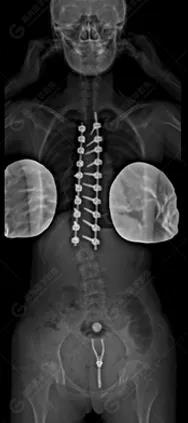

15歲女性,發(fā)現(xiàn)特發(fā)性脊柱側(cè)彎3年,于2019年1月23日來(lái)到廣東高尚醫(yī)學(xué)影像診斷中心行EOS檢查,2019年2月行手術(shù)治療后多次到中心行EOS復(fù)查。

2020-01-17

脊柱側(cè)彎最重要一個(gè)臨床參數(shù)是側(cè)彎角(Cobb角),目前臨床公認(rèn)的Cobb角>10 °診斷為脊柱側(cè)彎;如Cobb角進(jìn)行性持續(xù)性增加>40 °需要手術(shù)矯正治療。

本例患者胸椎右側(cè)彎,Cobb角(T6/T12)為47°,遂行手術(shù)矯正治療。術(shù)后多次隨訪的Cobb角(T10/L3)為12°-15°之間,較術(shù)前明顯縮小。